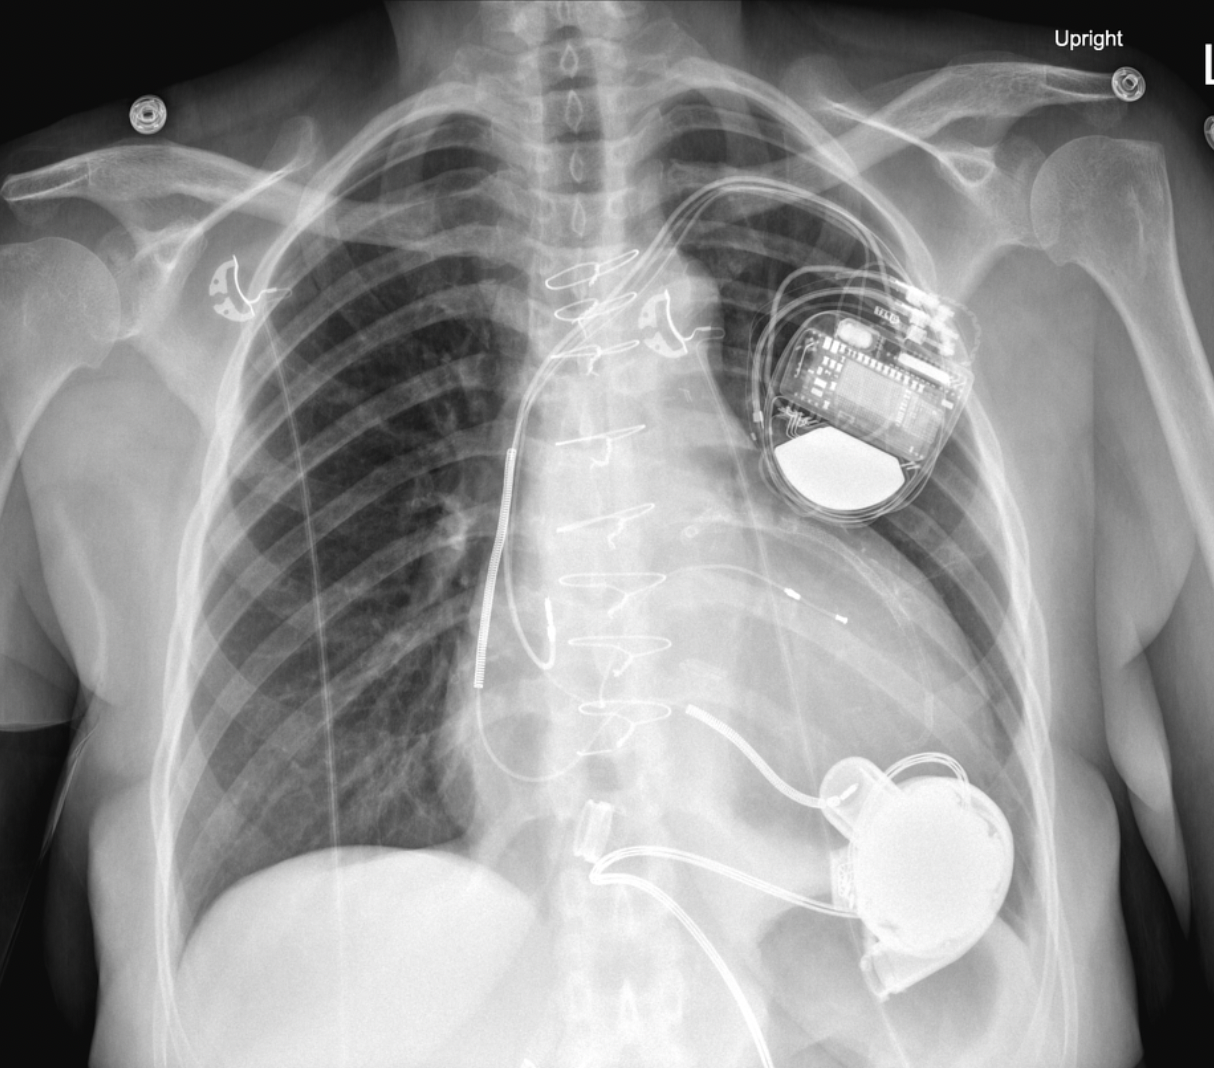

-Dual chamber ICD

-LVAD implanted